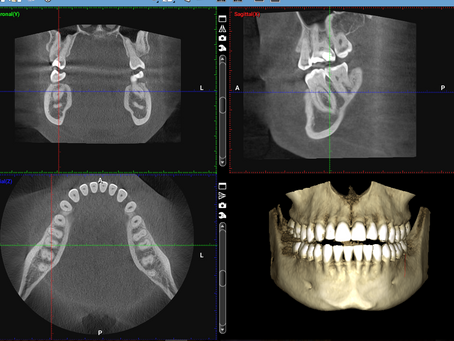

Revolutionizing Dental Implant Planning with CBCT Imaging

Dental implants have come a long way since their inception in the 1960s. From traditional x-rays to advanced technology, the world of...